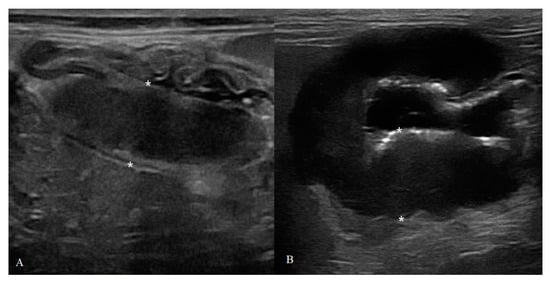

Figure 6. Different localization in gastric feline HGAL: (A) focal: a 7-year-old cat with a transmural mass (11.4 mm) with mixed echogenicity and loss of wall layers; (B) diffuse: severe hypoechoic thickening (20.8 mm) of gastric body with complete loss of normal layers in a cat 12-year-old cat.